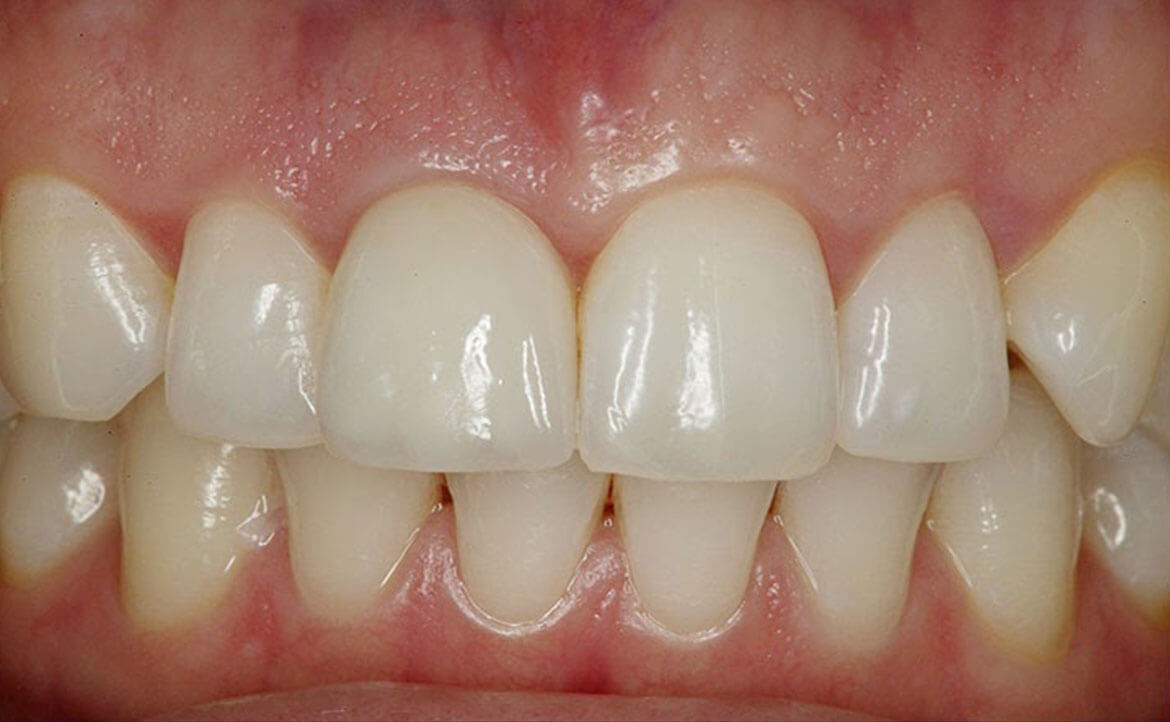

Un tale pezzo protesico ripristina l'integrità delle arcate dentarie. Una protesi mobile correttamente realizzata migliorerà esteticamente i lineamenti del viso del paziente, consentirà il ripristino della funzione masticatoria e migliorerà la fonazione.

Oltre al ripristino estetico della dentatura, il ponte dentale previene le complicazioni che possono derivare dalla mancanza di un dente. Una volta applicato, completerà il normale processo di masticazione e migliorerà la funzione fonetica.